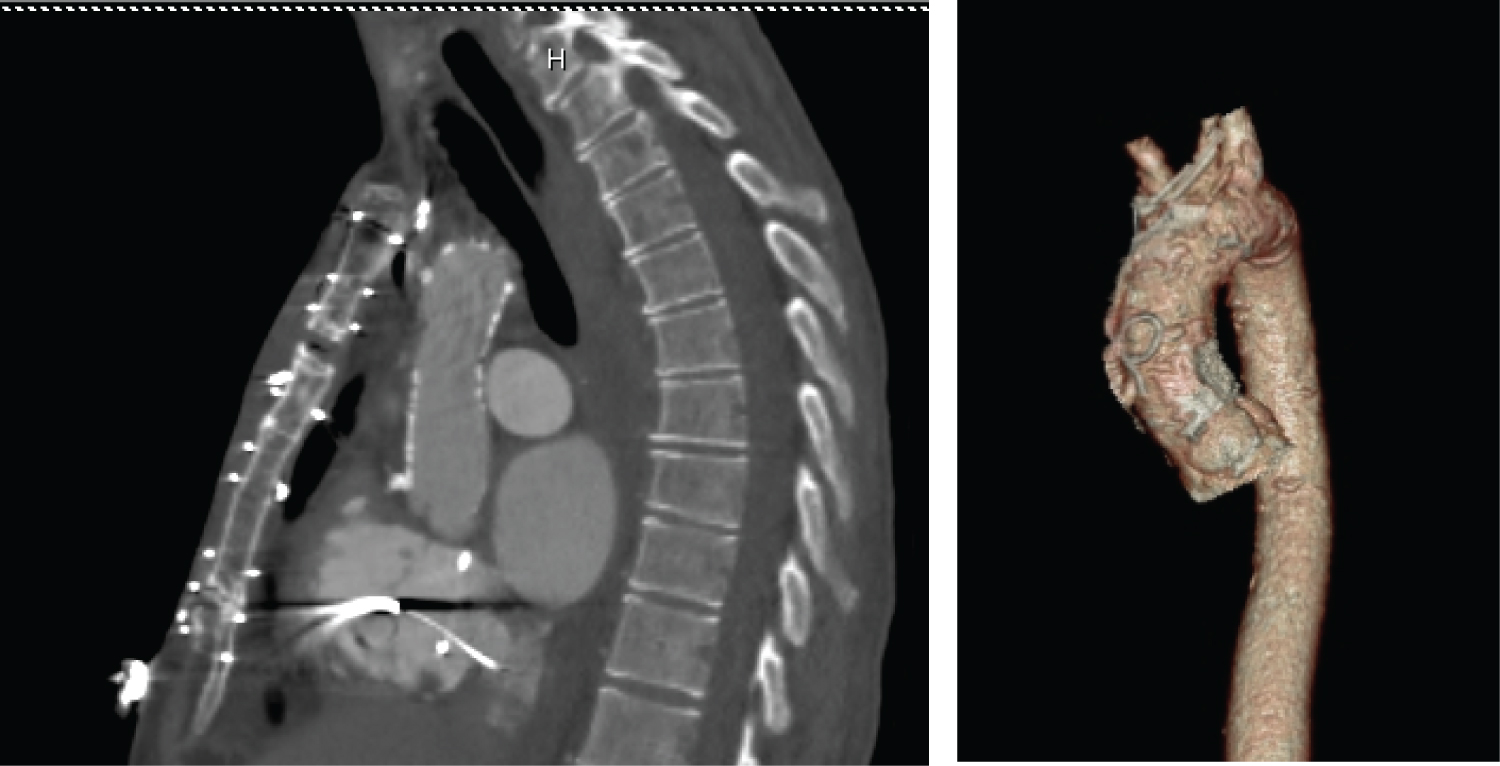

After a multidisciplinary case conference, it was recommended that patient should undergo aortic valve replacement. Patient underwent cardiac CT that showed near porcelain ascending aorta (Figure 2). It also revealed close proximity of LIMA to aorta and sternum. Treatment options for this patient at this time were either TAVR vs. apical aortic conduit placement. Patient underwent implantation of dual-chamber ICD for secondary prophylaxis of sudden cardiac death. During this procedure, atrial pacing was performed up to 180 bpm that showed one to one AV conduction with continued preexcitation. Patient was started on amiodarone to avoid recurrence of ventricular arrhythmias. Thereafter, he underwent TAVR with 26 mm sapient transcatheter aortic valve.

Figure 2: Cardiac CT demonstrating near porcelain aorta. View Figure 2